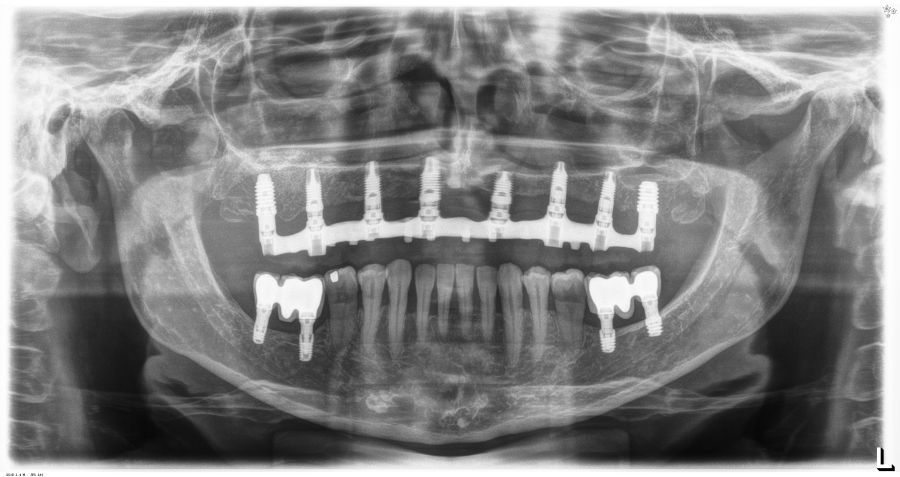

La media de la pérdida ósea mesial de los implantes estudiados en el final del período de seguimiento a los 10 años fue de 0,94mm (+/- 0,28) mientras que la media de la pérdida ósea distal fue de 0,77 mm (+/- 0,17). Durante el tiempo de seguimiento no se registró ningún fracaso en los implantes estudiados. La media de la anchura ósea a los 10 años fue de 6,26 mm (+/- 1,08). En la figura 4 se observa la diferencia entre la anchura inicial, la lograda tras la consolidación del injerto y tras los 10 años de seguimiento. En las figuras 5-19 se muestra uno de los casos incluidos en el estudio.